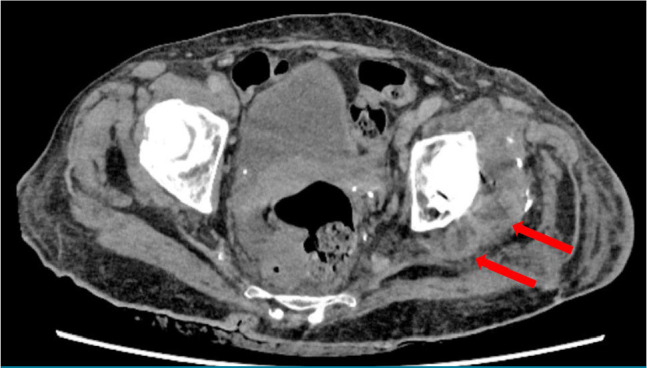

假体周围关节感染(PJI)仍然是全髋关节置换术(THA)后的一个具有挑战性的并发症,通常通过两阶段翻修来管理,这可能导致显著的发病率。在这篇文章中,我们提出一个罕见的病例肠炎沙门氏菌PJI,最初表现为假体髋关节脱位。术前使用血培养瓶进行髋关节抽吸可以早期识别细菌并指导靶向抗菌治疗。患者使用固定良好的定制关节间隔器(CUMARS)结构进行翻修THA,并使用靶向抗生素骨水泥。一年的随访表明感染成功根除,植入物固定稳定,功能预后良好。总之,该病例强调了诊断髋关节抽吸的重要性,并强调了CUMARS技术作为治疗由肠炎沙门氏菌等非典型生物引起的罕见PJIs的有效和持久解决方案的潜力。

Periprosthetic joint infection (PJI) remains a challenging complication following total hip arthroplasty (THA), commonly managed through a two-stage revision which can lead to significant morbidity. In this article, we present a rare case of Salmonella enteritidis PJI, initially presenting as prosthetic hip dislocation. Preoperative hip aspiration utilizing blood culture bottles enabled early identification of the organism and guided targeted antimicrobial therapy. The patient underwent revision THA using a well-fixed custom-made articulating spacer (CUMARS) construct, with targeted antibiotic-loaded bone cement. One-year follow-up demonstrated successful eradication of the infection, stable implant fixation, and good functional outcomes. In conclusion, this case underscores the importance of diagnostic hip aspiration and highlights the potential of the CUMARS technique as an effective and durable solution for managing rare PJIs caused by atypical organisms such as Salmonella enteritidis.